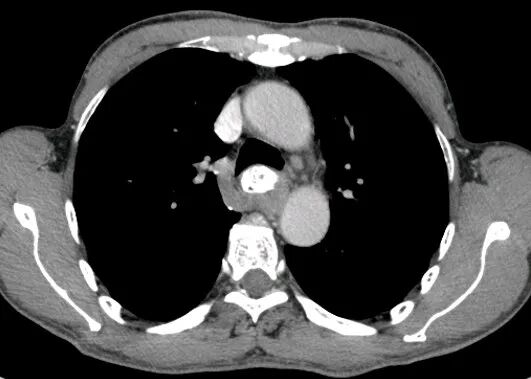

胃癌

进展期胃癌CT检查有利于观察病变的侵犯范围和淋巴结转移情况

早期胃癌多数病人无明显症状,少数人有恶心、呕吐或是类似溃疡病的上消化道症状。疼痛与体重减轻是进展期胃癌最常见的临床症状。病人常有较为明确的上消化道症状,如上腹不适、进食后饱胀,随着病情进展上腹疼痛加重,食欲下降、乏力。